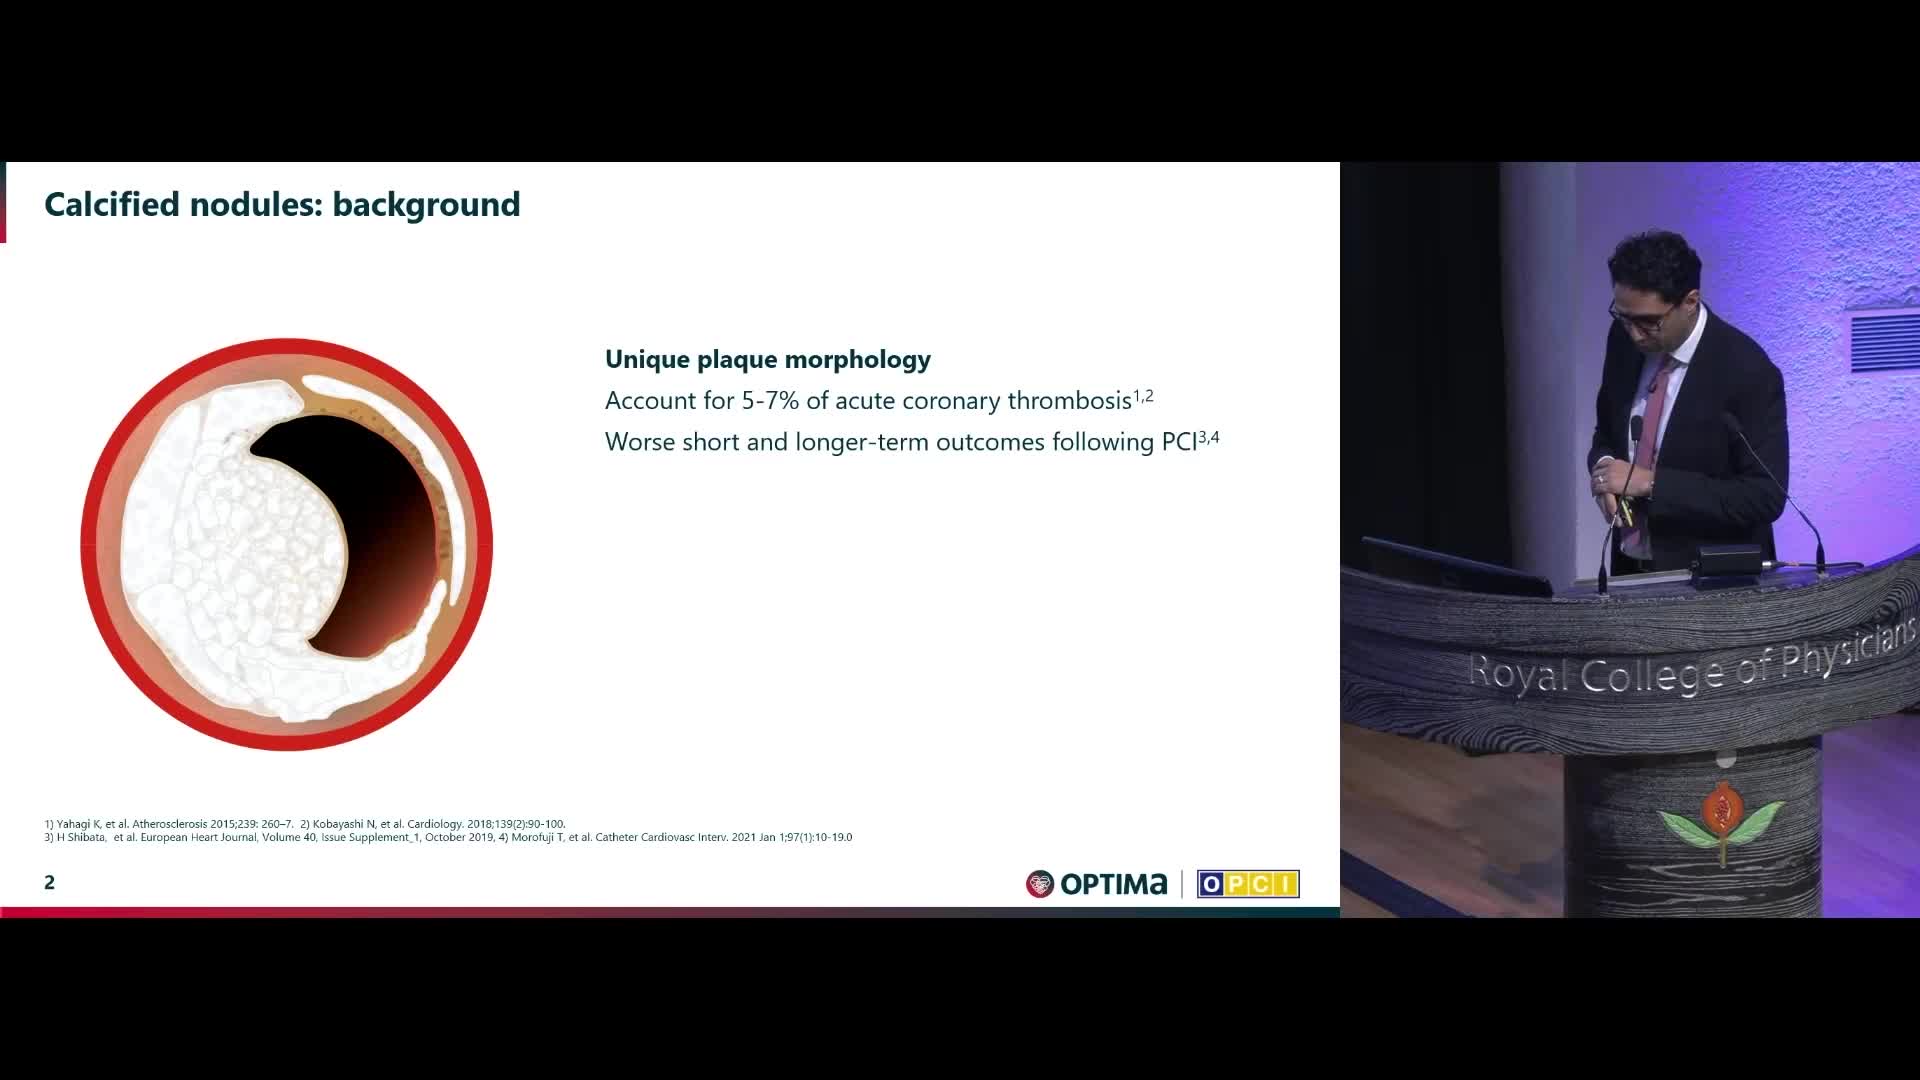

Session 2: Coronary calcium – too hard to crack?

Treatment of coronary arterial calcium (CAC) has being redefined. We explore the interaction between CAC and patient...